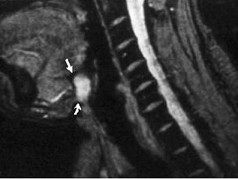

8.患者腫塊圖像及影像學檢查結果見下圖,本患者應考慮為  (    )